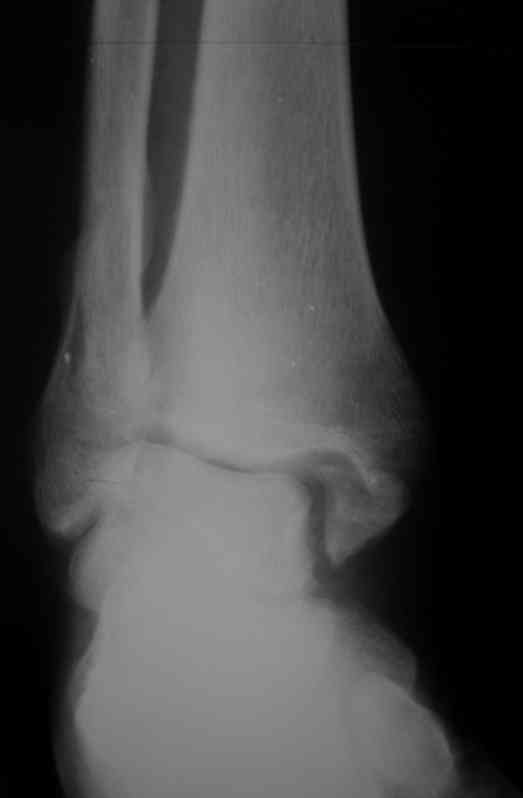

Неправильно консолидированный перелом лодыжек |

Обратился больной 23 года, травма 4 месяца назад - закрытый перелом наружной, внутренней лодыжки правой голени. Лечился консервативно, гипсовой иммобилизацией 8 недель, после снятия последней прошел курс восстановительного лечения. Беспокоят боли в области правого голеностопного сустава больше в проекции внутренней лодыжки, к вечеру. Отечность области сустава при физических нагрузках.

Походка не изменена. Контуры правого голеностопного сустава сглажены. Имеется вальгусная установка правой пяточной кости. Объем движений в голеностопном суставе подошвенное / тыльное сгибание 50/0/80, безболезненные. Посоветуйте что делать в данной ситуации.

Мне видится следующий вариант решения данной деформации: Восстановление нормальной анатомии голеностопного сустава - остеотомия малоберцовой кости и внутренней лодыжки, удалить все рубцы из области дистального межберцового синдесмоза, восстановить длину и устранить ротационное смещения наружной лодыжки.( встанет ли таранная кость на место?), фиксация наружной лодыжки пластиной, внутренней - винтами, дистального межберцового синдесмоза винтом. ЭОПом не располагаем. Что вы посоветуете? Где могут быть - технические трудности, <подводные камни>.